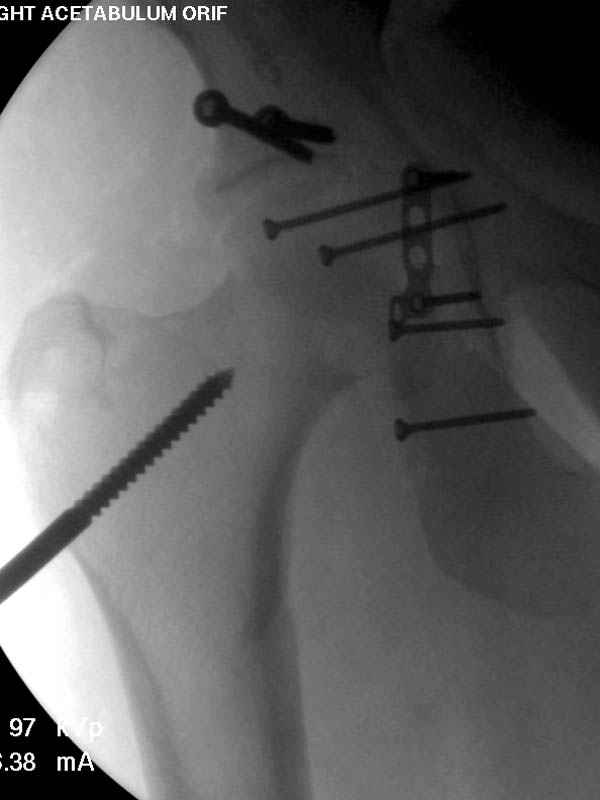

По возможности вышлите снимки, сканы таза до

реконструкции, интраоперационные.

По снимку создается впечатление о высоком поперечном переломе, задней колонны, стенки; почему не пользовались *magic screw*?

Латеральное положение облегчает проведение тракции через вертел, за 5 мм стержень за вертел (грузом через тракционное приспособление), на обычном рентгенопрозрачном операционном столе, а для положения на животе, наверное, Judet Table более приемлем, потому что там имеется латеральное тракционное устроиство.

Там множество обычных 2.7 мм шурупов, потом идет фиксация основными пластинами.

Снимки здесь....